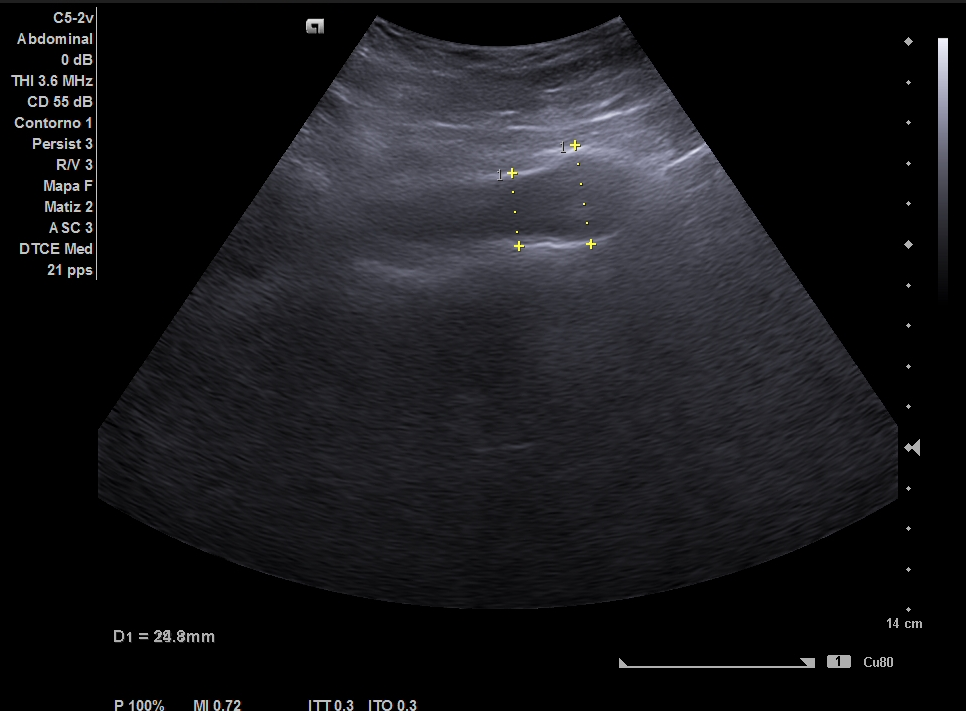

Parenquima hepatico sin alteraciones, vesícula biliar sin imagenes hiperecoénicas en interior. Pancreas visible en parte, sin alteraciones. Asimetría entre ambos riñones compatible variante de la normalidad RI. Llama la atención dilatación ilíaca derecha al comparar con contralateral y con aorta abdominal distal. Compatible con dilatación aneurismática ilíaca derecha.

Abdominalgia en estudio + Dilatación aneurismática ilíaca derecha.

El diagnóstico diferencial del Aneurisma Ilíaca con: Displasia fibromuscular u otra patología del tejido conectivo, lúes o tuberculosis entre otros. Toda dilatación que sobrepase el 50% del diámetro del vaso se considera aneurismática. Por la edad no se plantea el origen ateromatoso.